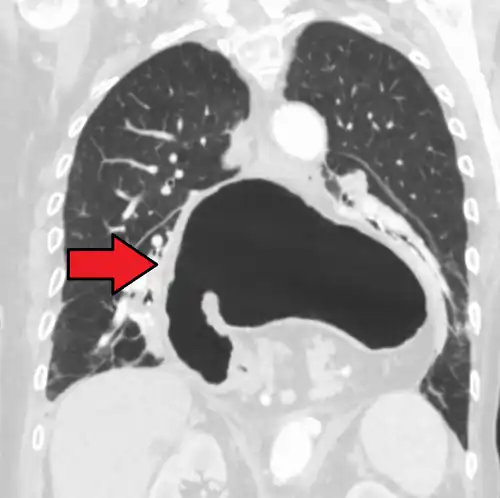

A hiatal hernia as seen on CT -

A large hiatal hernia as seen on CT imaging -